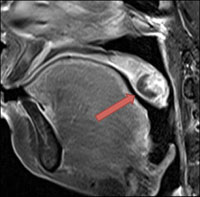

中咽頭癌 Ct Mri検査 がん 腫瘍 ピーチクパープル Yahoo ブログ

9回目pet ct Mri検査と血糖値 仕事をしながら中咽頭癌と闘う美容

術後4ヶ月 Ct検査 中咽頭癌闘病にっき 3歳0歳2児のママ

中咽頭がん 治療後6年半の検査結果 仕事をしながら中咽頭癌と闘う

父の癌細胞が消滅したct Mri画像 難病 末期癌からの生還